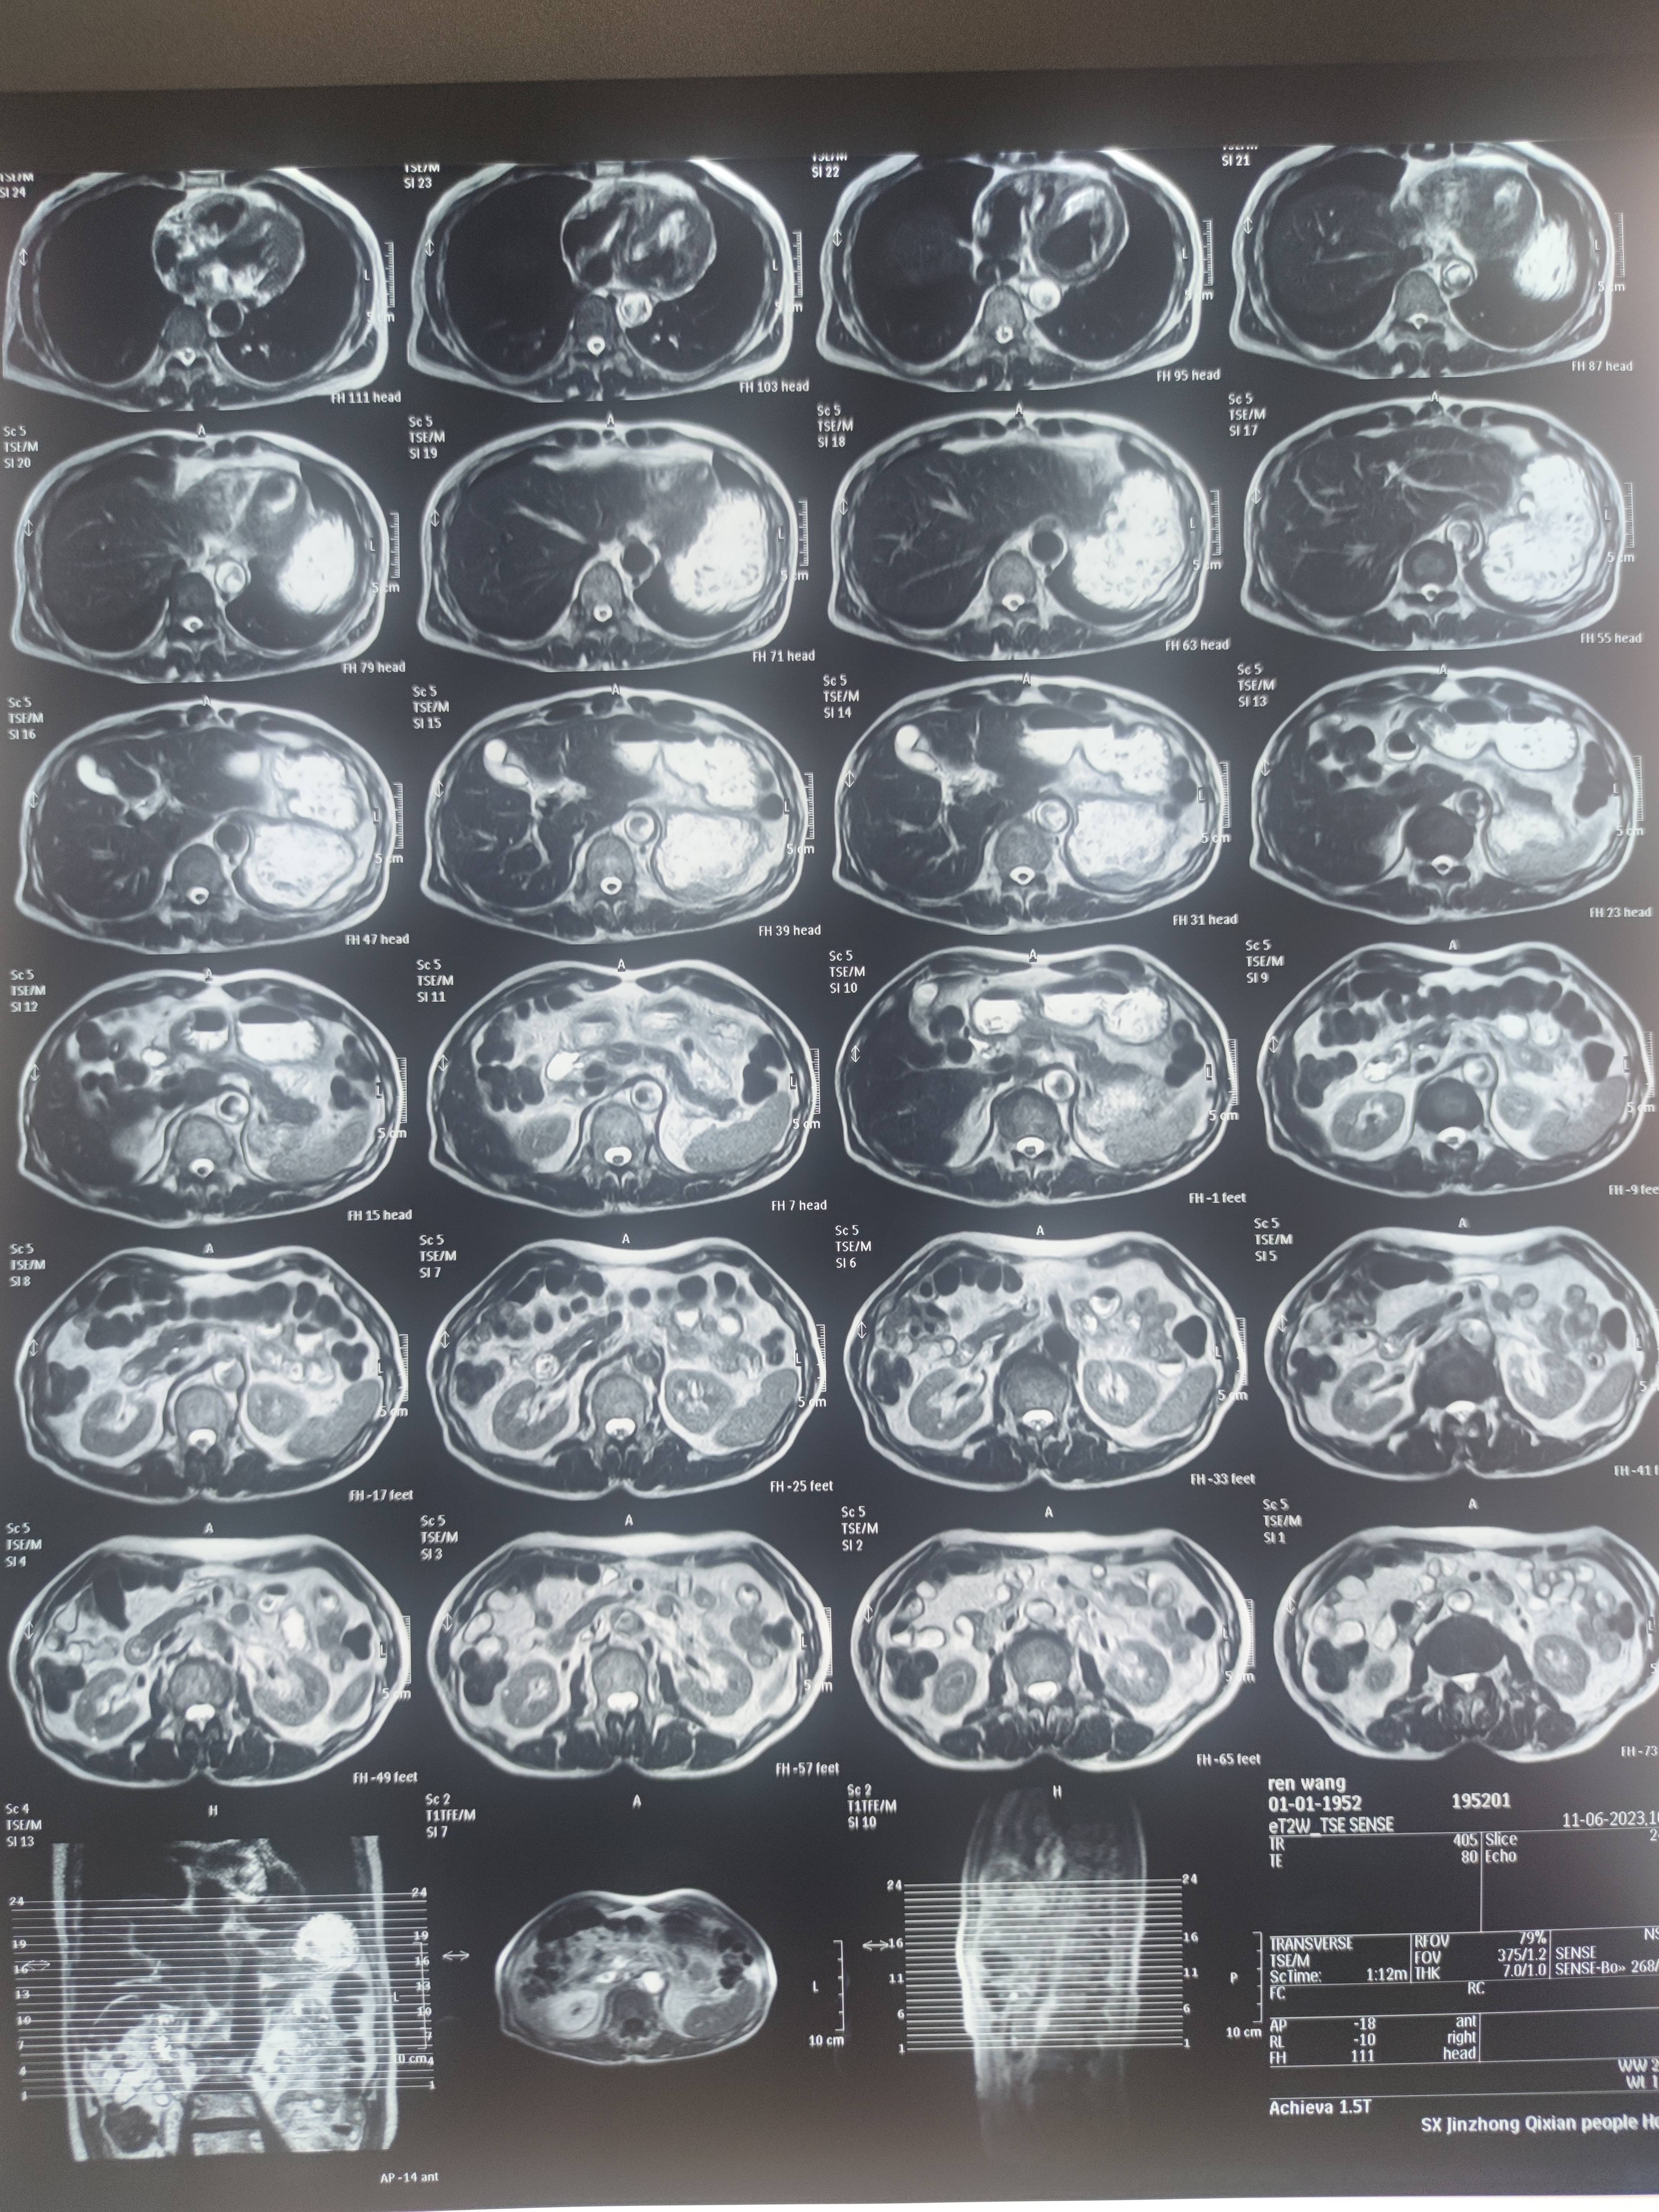

四月份癌胚抗原还是5.6,这个月到8了,持续升高。做了核磁增强,左侧桥小脑角哪有个地方不确定。肝脏核磁平扫弥散有两个点状高信号,转移也排不了,胃肠镜正常,左颈部有个变圆的淋巴结,保险点是不该加个化疗药了?咨询了陈波主任,等结果的吧!图片